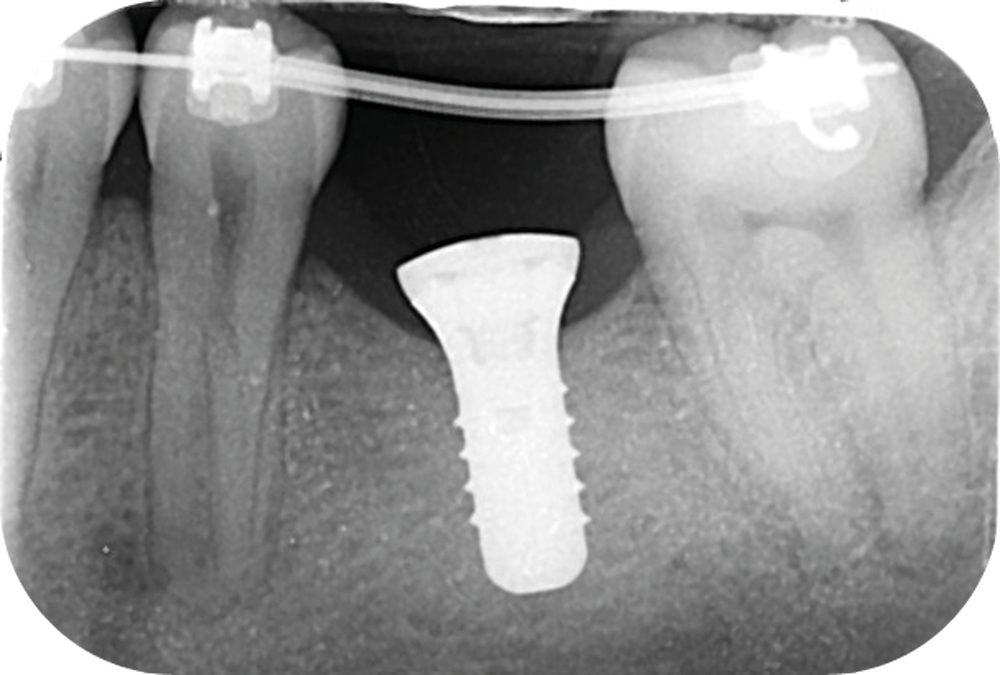

Cette version, quand elle se produit, modifie les espaces interdentaires et complique l’hygiène proximale des patients. Des caries peuvent alors se développer en interproximal sans que cela soit forcément visible à l’examen visuel (fig. 3 et 4). Les radios de type bite-wing (rétro-coronaires) prennent alors tout leur sens (fig. 5 et 6).

La prise en charge de ces édentements nécessite un examen complet du site implantaire et de l’environnement [16]. Les conséquences du non-remplacement rapide que nous venons d’énumérer sont à prendre en compte et à corriger pour une intégration optimale de la restauration prothétique implantaire. Ainsi, des corrections orthodontiques peuvent être nécessaires avant ou pendant la thérapeutique implantaire.

Le temps de l’ostéointégration, des versions ou migrations sont aussi possibles et le recours à des dispositifs de maintien de l’espace peut se révéler indispensable (fig. 22 et 23).